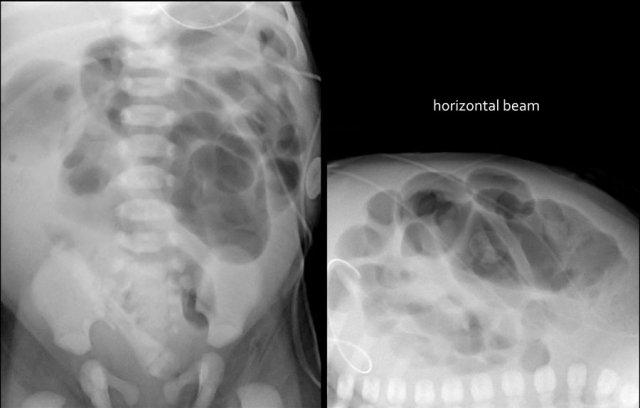

Các dấu hiệu bao gồm:

- Nhiều quai ruột non giãn

- Khí trong thành ruột (Pneumatosis intestinalis).

- Tràn khí ổ bụng (Pneumoperitoneum).

Chẩn đoán:

Viêm ruột hoại tử (NEC) có thủng ruột.